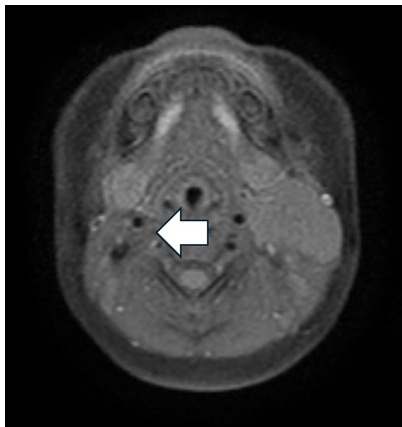

为了进一步评估,研究人员在深度镇静下为患儿进行了颈部磁共振成像(MRI)增强检查。MRI显示一个3×2.5×2厘米的肿块,在T1加权图像上呈等信号,在T2加权图像上呈稍高信号。

脂肪抑制序列没有信号抑制,DWI/ADC序列显示明显的信号限制。

注射对比剂后,可见一些供应病变的血管,但没有明显的对比增强。

病变位于左腮腺前方,两者之间有可识别的分界平面。病变向内侧延伸,抵着C4-C5水平的颈部神经血管束,但没有明显压迫;向外侧抵着胸锁乳突肌。